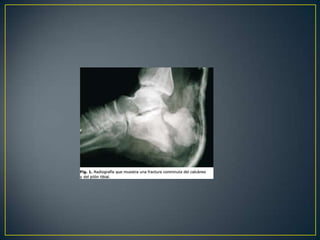

ANATOMÍAEl calcáneo es un hueso cuboideoque, colocado bajo el astrágalo, apoya directamente contra el suelo.Anatomía LatargetRuiz Liar pag 862 4ta edición

IIIIVVRADIOGRAFÍASSIMPLES 		    TOMOGRAFÍApreoperatoria

TAC

II  BTC  preoperatoriaIncongruencia subtalica  post.   :  90 %Conflicto maleolar externo            :  80 %Lesión calcáneo-cuboidea             :  40 %

Crosby y fitzgibbon y de Sanders Tipo I son fracturas no desplazadas. Tipo II son dos partes o dividir las fracturasTipo III son de tres partes o las fracturas de la depresión de división. Tipo IV fueron de cuatro partes o muy conminutas fracturas articulares. Basada en TAC: lesiones complejas